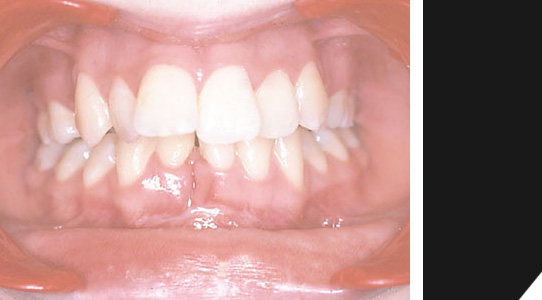

Der selbe Patient nach der erfolgreichen Behandlung, mit harmonisch ausgeformter Zahnreihe. Die Kieferfehlstellung im Unter- und Oberkieferbereich wurde behoben. Die Schneidezähne im oberen Bereich sind wieder gerade.